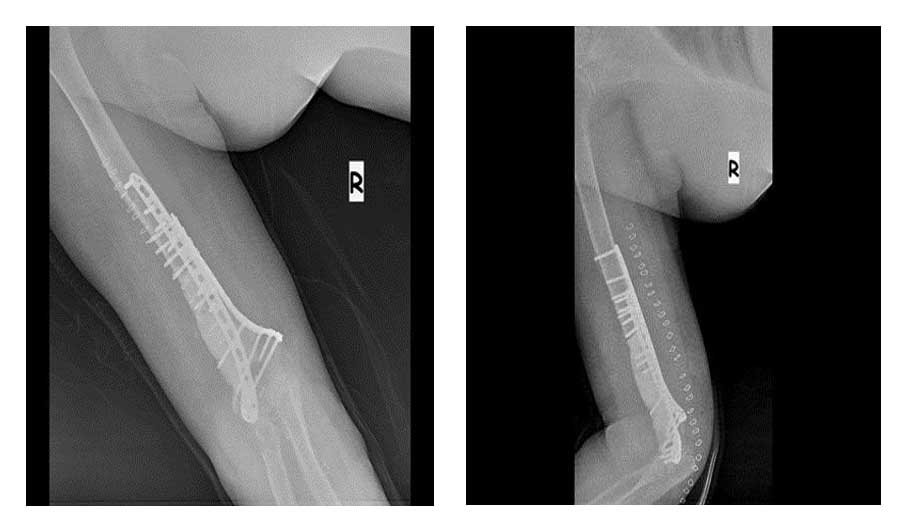

Tümörlü bölge temizlenerek oluşan boşluk kemik çimentosu ile dolduruldu ve bölge iki adet titanyum anatomik plak ile güçlendirildi.

Ameliyat Sonrası: Röntgende tümörün temizlendikten sonra oluşan boşluğun kemik çimentosu ile doldurulması ve iki adet titanyum plak ile güçlendirilmesi görülmekte.